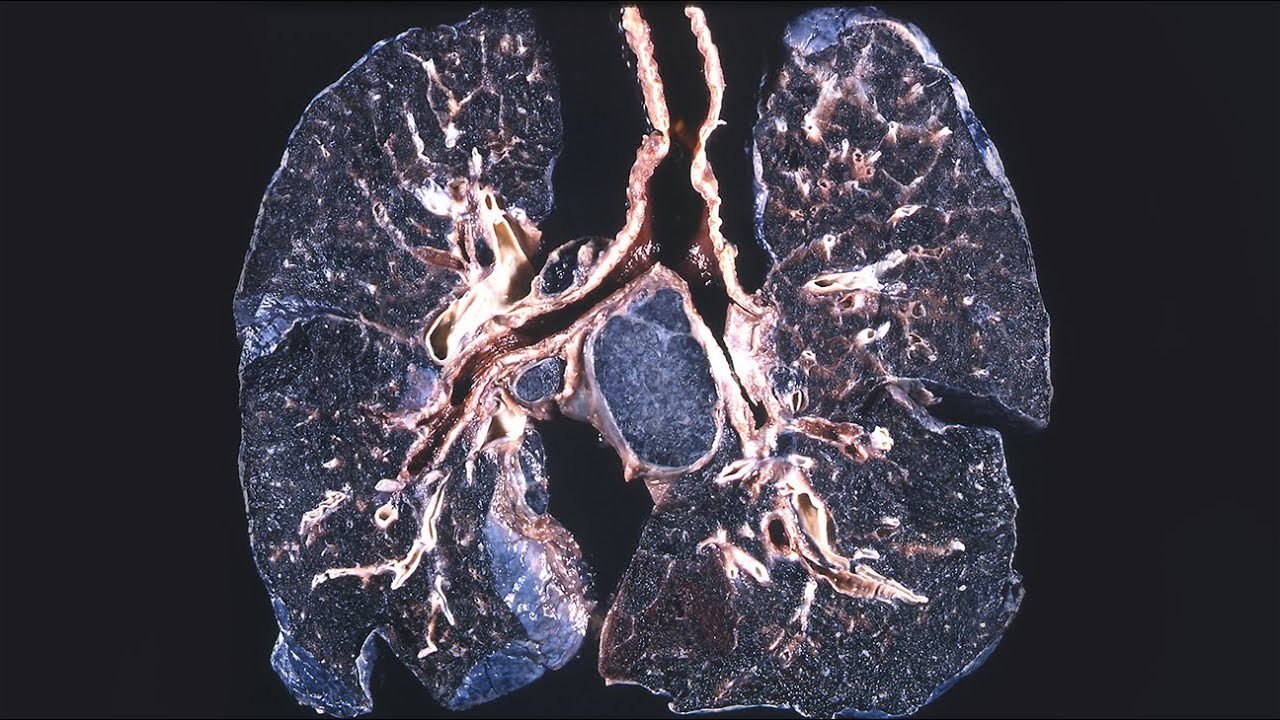

Mayo-klinikan asiantuntijat väittävät, että 96–98 % keuhkokyhmistä on hyvänlaatuisia, jopa ihmisillä, joilla on riskitekijöitä, kuten tupakointi. David E. Midtown, tämän laitoksen keuhkosairauksien erikoislääkäri, selittää: ”Valtaosa näistä kyhmyistä on arpikudosta aiemmin sairastetuista keuhkoinfektioista, eivätkä ne yleensä aiheuta oireita.”

Yleiset syyt ja koktsidioidomikoosin tapaus

Yleisimpiä syitä kyhmien muodostumiseen ovat infektiot, kuten laakson kuume , joka on levinnyt Yhdysvaltojen lounaisosassa. Tohtori Janice E. Blair , tartuntatautien asiantuntija Mayo-klinikalta , selittää: ”Laakson kuume on infektio, jonka aiheuttaa Coccidioides-sieni, joka elää tämän alueen aavikkomailla.”

Tämän loisen itiöiden hengittäminen voi aiheuttaa infektion ja jättää pysyviä vaurioita keuhkoihin, yleensä ilman näkyviä oireita. Tohtori Blair huomauttaa, että noin 60 % tartunnan saaneista on oireettomia eivätkä tiedä keuhkovaurioistaan. On olemassa verikokeita, joilla voidaan havaita immuunivaste koktsidioosiin , mutta nämä kokeet eivät osoita, onko se ollut välitön syy vaurioon.